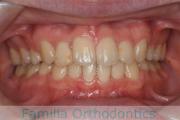

No.23V-132

- 主な症状:

- 開咬

- 年齢:

- 16歳

- 性別:

- 男性

- 抜歯部位

- 上:

- 88

- 下:

- 主な使用装置:

- FEA

- 治療にかかった費用:

- 87万円

開咬なので治療したいとのことで来院されました。受け口傾向のある開咬(前歯が咬み合わない)でしたので、下の親知らずを抜歯してマルチブラケット法にて治療を行いました。約1年半、20回程度の通院が必要でした。開咬は舌の癖の影響が強く、後戻りのリスクが高いケースといえます。